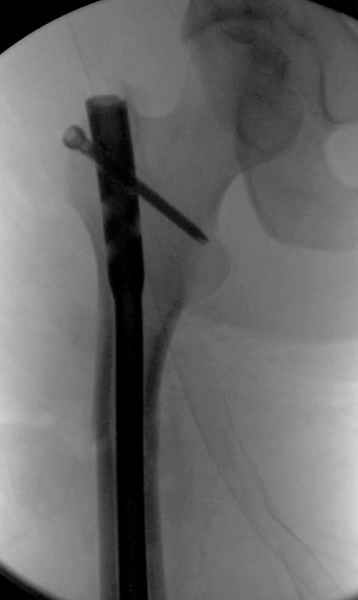

Больной долго оставался нестабильным, только на 14 день удалось заменить на антеградный интромедуллярный штифт TFN (trochanteric femoral nail) SmithNephew. После неудачной попытки закрытой репозиции, несмотря на использование "joystick", проксимальный стержень от

наружного фиксатора, (перелом начал срастаться) репозицию провели из малого доступа, затем остальные этапы операции.

Случай был представлен из-за того, что больного оперировали после наружной фиксации и был риск инфекцирования через места проведения стержней (на снимках), прошло больше 3 месяцев, выписан из амбулаторной службы из-за отсутсвия надобности дальнейшего наблюдения.